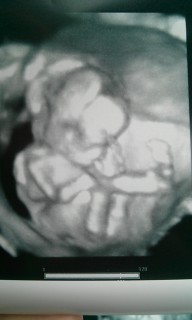

頭の後ろで手を組んで、すごくくつろいでいるように見えます!! この様子が私にそっくりだと友人たちに言われ、ウケました! (≧∀≦)

まだ性別は、はっきりわかりませんでしたが顔を手で覆っている姿が撮れました!次回は顔を見せてくれるといいです。大きさは14cmと書いてあります。